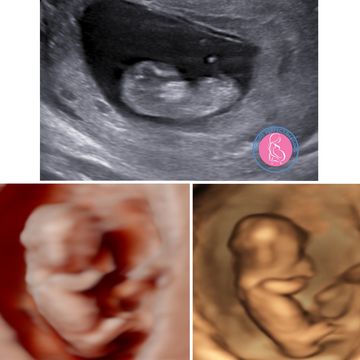

This scan is provided to confirm pregnancy, estimate the gestational age, and confirm whether it is a single or multiple pregnancy.

Watch baby grow during the entire pregnancy!